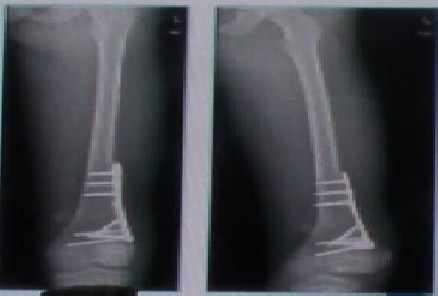

外院拍片显示腰1椎骨质疏松性椎体压缩骨折。伤后2个月仍感腰部疼痛,无法离床。查体:腰1椎体棘突扣痛(+)。下肢感觉运动无异常。

伤后2个月行“腰1椎体球囊扩张、后凸成型术”。术后患者感觉腰痛明显缓解,术后3天即离床活动。下肢感觉运动无异常,大小便自解。术后半个月复查腰椎正侧位片,显示骨水泥在椎体内分布可,无明显渗漏。